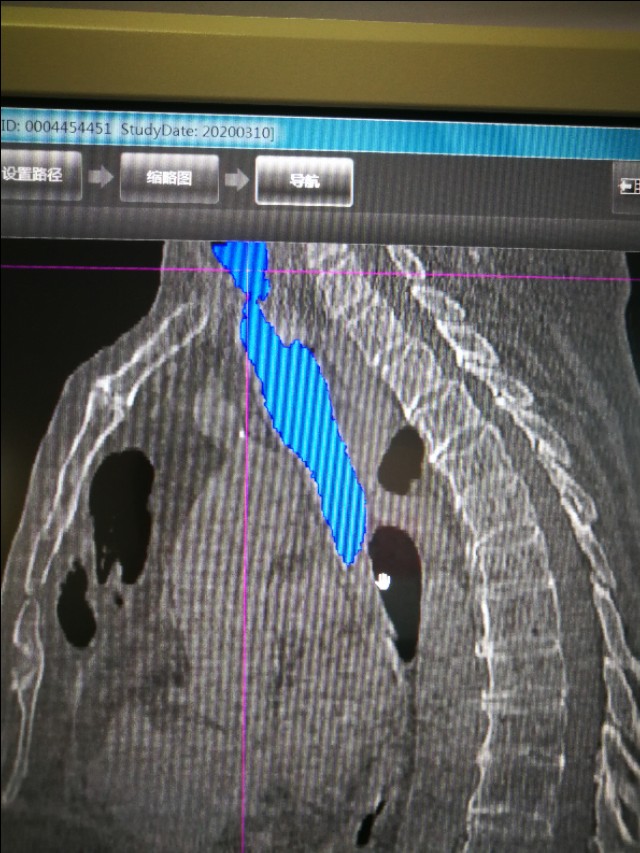

临床医生一看,他吸气有“三凹征”,这是大气道梗阻的表现啊。CT检查也证实了这一点。

这么窄的气道,肯定会气不够用啊。

我们想到了一年前他曾经插管上有创呼吸机,可能当时的切口,愈合后形成了瘢痕,瘢痕挛缩导致气道狭窄。

气管镜下可以更直观的看到气管到底多狭窄。只剩下几毫米的小孔了。